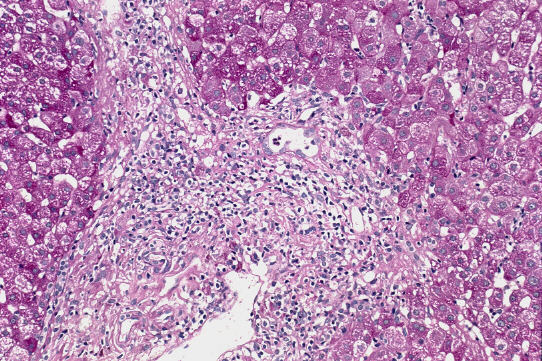

標 本;HE、Masson-trichrome、PAS&鍍銀の4染色

- 小葉構造;保持されている[F1〜(2)]、一部のP-Pのapproximation

- 門脈域;中等度の線維性拡大、中等度の単核球主体の炎症性細胞浸潤、リンパ様濾胞、明らかな小葉間胆管の障害像、periductal fibrosis、細胆管増生

- 実質域;acute yellow collapse cell を含む巣状壊死を散在性にみる、好酸体(+)、肝細胞の風船様膨化と明調化(部分的)、肝細胞の大小不同、肝細胞核の大小不同、大滴性脂肪沈着を部分的に軽度にみる、核内空胞、ロゼット形成(偽腺管構造)、実質内に細線維の伸長、一部の限界板の削り取り壊死、銅の沈着はなし。

病理組織診断;Acute exacerbation of chronic hepatitis [AIH]

A(2)〜3/F1〜(2) [AIH]

病 因;元来、軽度の慢性炎に急性増悪が加わったAIH